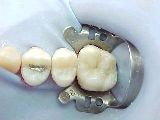

ANTES DEPOIS

Caso acima, em outro ângulo, no momento da cimentação do ONLAY